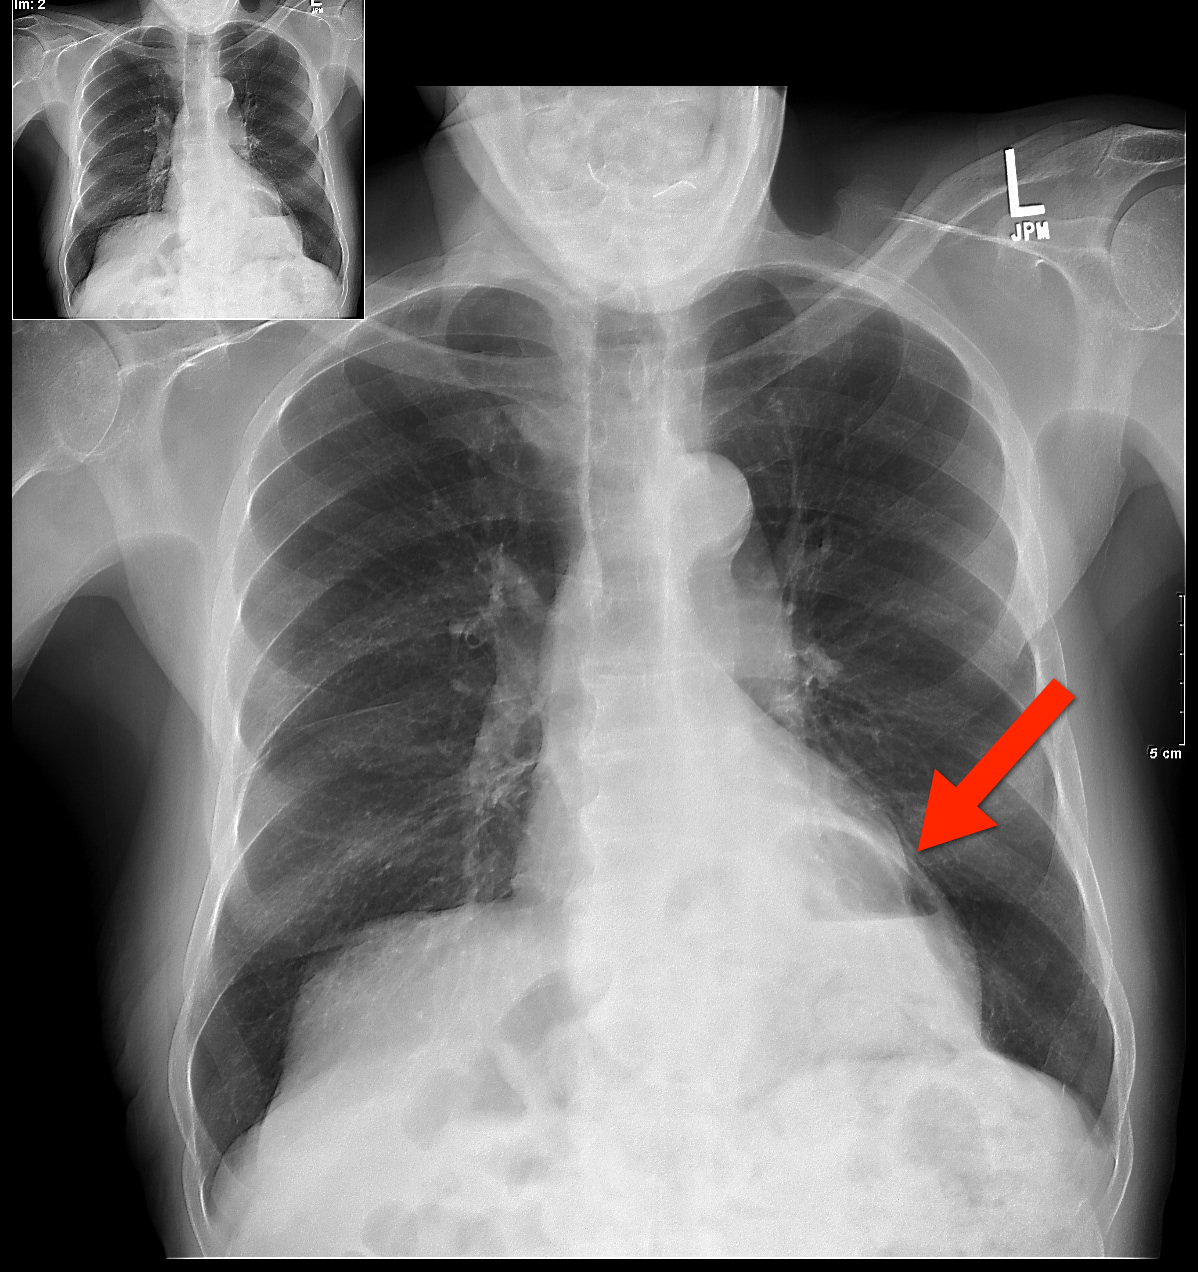

From www.wikidoc.org

Hiatus hernia chest x ray wikidoc What Does A Chest Hernia Look Like a hernia occurs when an internal part of the body pushes through a weakness in the muscle or surrounding. a hiatal hernia happens when the upper part of the stomach bulges through the large muscle that separates the. hernia pictures and info for some of the most common hernia types give more tools to. a hernia. What Does A Chest Hernia Look Like.

Congenital diaphragmatic hernia chest x ray wikidoc What Does A Chest Hernia Look Like a hernia usually happens in your abdomen or groin, when one of your organs pushes through the muscle or. less common (but possible) symptoms. hernia pictures and info for some of the most common hernia types give more tools to. many hernias occur in the abdomen between your chest and hips, but they can also appear. What Does A Chest Hernia Look Like.

From www.youtube.com

Hiatal Hernia Explanation of Chest XRay Findings YouTube What Does A Chest Hernia Look Like a hernia usually happens in your abdomen or groin, when one of your organs pushes through the muscle or. hernia pictures and info for some of the most common hernia types give more tools to. a hiatal hernia happens when the upper part of the stomach bulges through the large muscle that separates the. a hernia. What Does A Chest Hernia Look Like.

Chest xray, Hiatus Hernia YouTube What Does A Chest Hernia Look Like a hernia occurs when an internal part of the body pushes through a weakness in the muscle or surrounding. a hiatal hernia happens when the upper part of the stomach bulges through the large muscle that separates the. The main symptoms of a hernia are pain and bulging in the affected area,. less common (but possible) symptoms.. What Does A Chest Hernia Look Like.